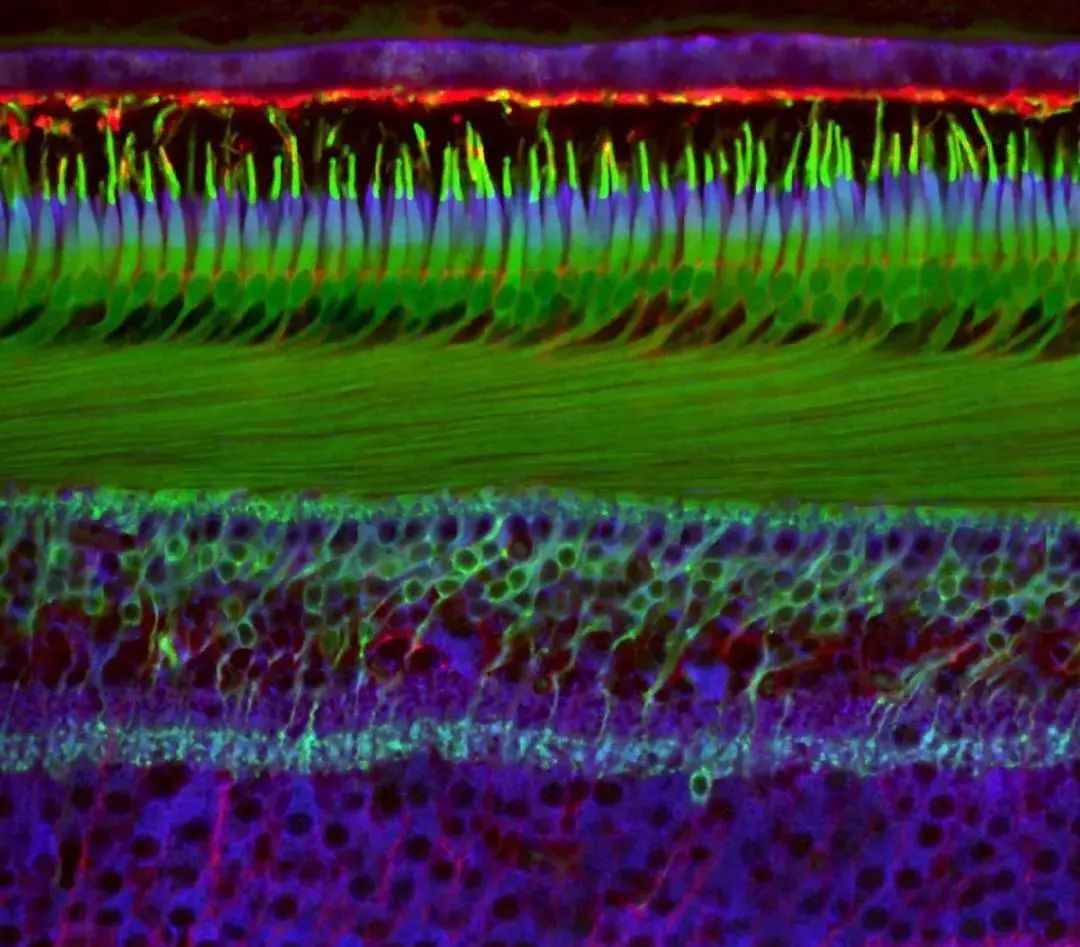

视网膜的中心区域

第 6 名:灵长类视网膜的中心区域(Hanen Khabou / 摄)Hanen Khabou 来自巴黎治疗学系视觉研究所

人类视网膜

第20名:人类视网膜(Nicolás Cuenca 和 Isabel Ortuño-Lizarán/ 摄)Nicolás Cuenca 和 Isabel Ortuño-Lizarán来自西班牙阿利坎特大学